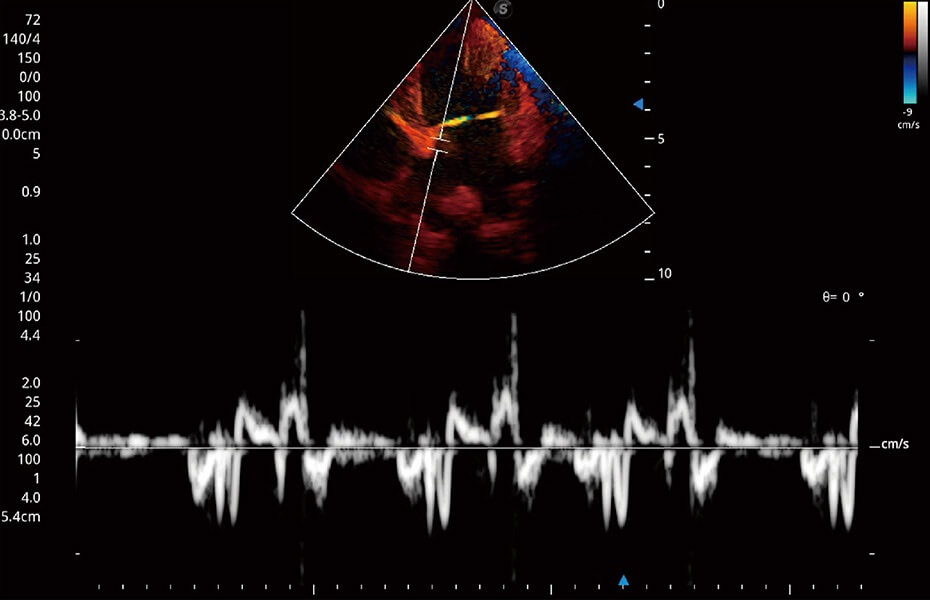

ProPet 60 作為一款高端臺式動物超聲設(shè)備,為動物醫(yī)生的日常診斷提供了一系列貼合動物臨床需求、解決臨床實際問題的高級成像功能。憑借全系列高清探頭,滿足醫(yī)生對腹部、心臟、生殖、淺表、肌骨等成像的所有需求,切實幫助您提升檢查效率,提高診斷信心。